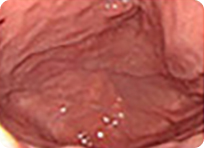

최근 위내시경의 해상도는 아래 사진과 같이 아주 뛰어난 상태로 1mm이하의 작은 병변도 확대해서 관찰이 가능합니다. 따라서 내시경 검사는 정상과 별 차이가 없어 보이는 미세한 조기 위암과, 조기 식도암 및 조기 대장암을 진단하는데 가장 정밀하면서 정확한 방법입니다.

위해상도 사진

아래 사진과 같이 5x5mm 크기의 작은 사각형을 실제 17인치 모니터에 꽉 차 보일만큼 정확하게 확대해서 관찰할 수 있으며 1mm 눈금보다도 작은 부분도 정확하게 관찰할 수 있을 정도로 정확합니다.

매우 작고 미세한 변화만을 보이는 조기위암들

풍부한 내시경 경험을 가진 의료진이 최신의 내시경 기계를 이용하여 세심한 관찰을 해야 위와 같은 매우 작은 조직 위암을 놓치지 않고 진단할 수 있습니다.

정상 위의 내시경 사진